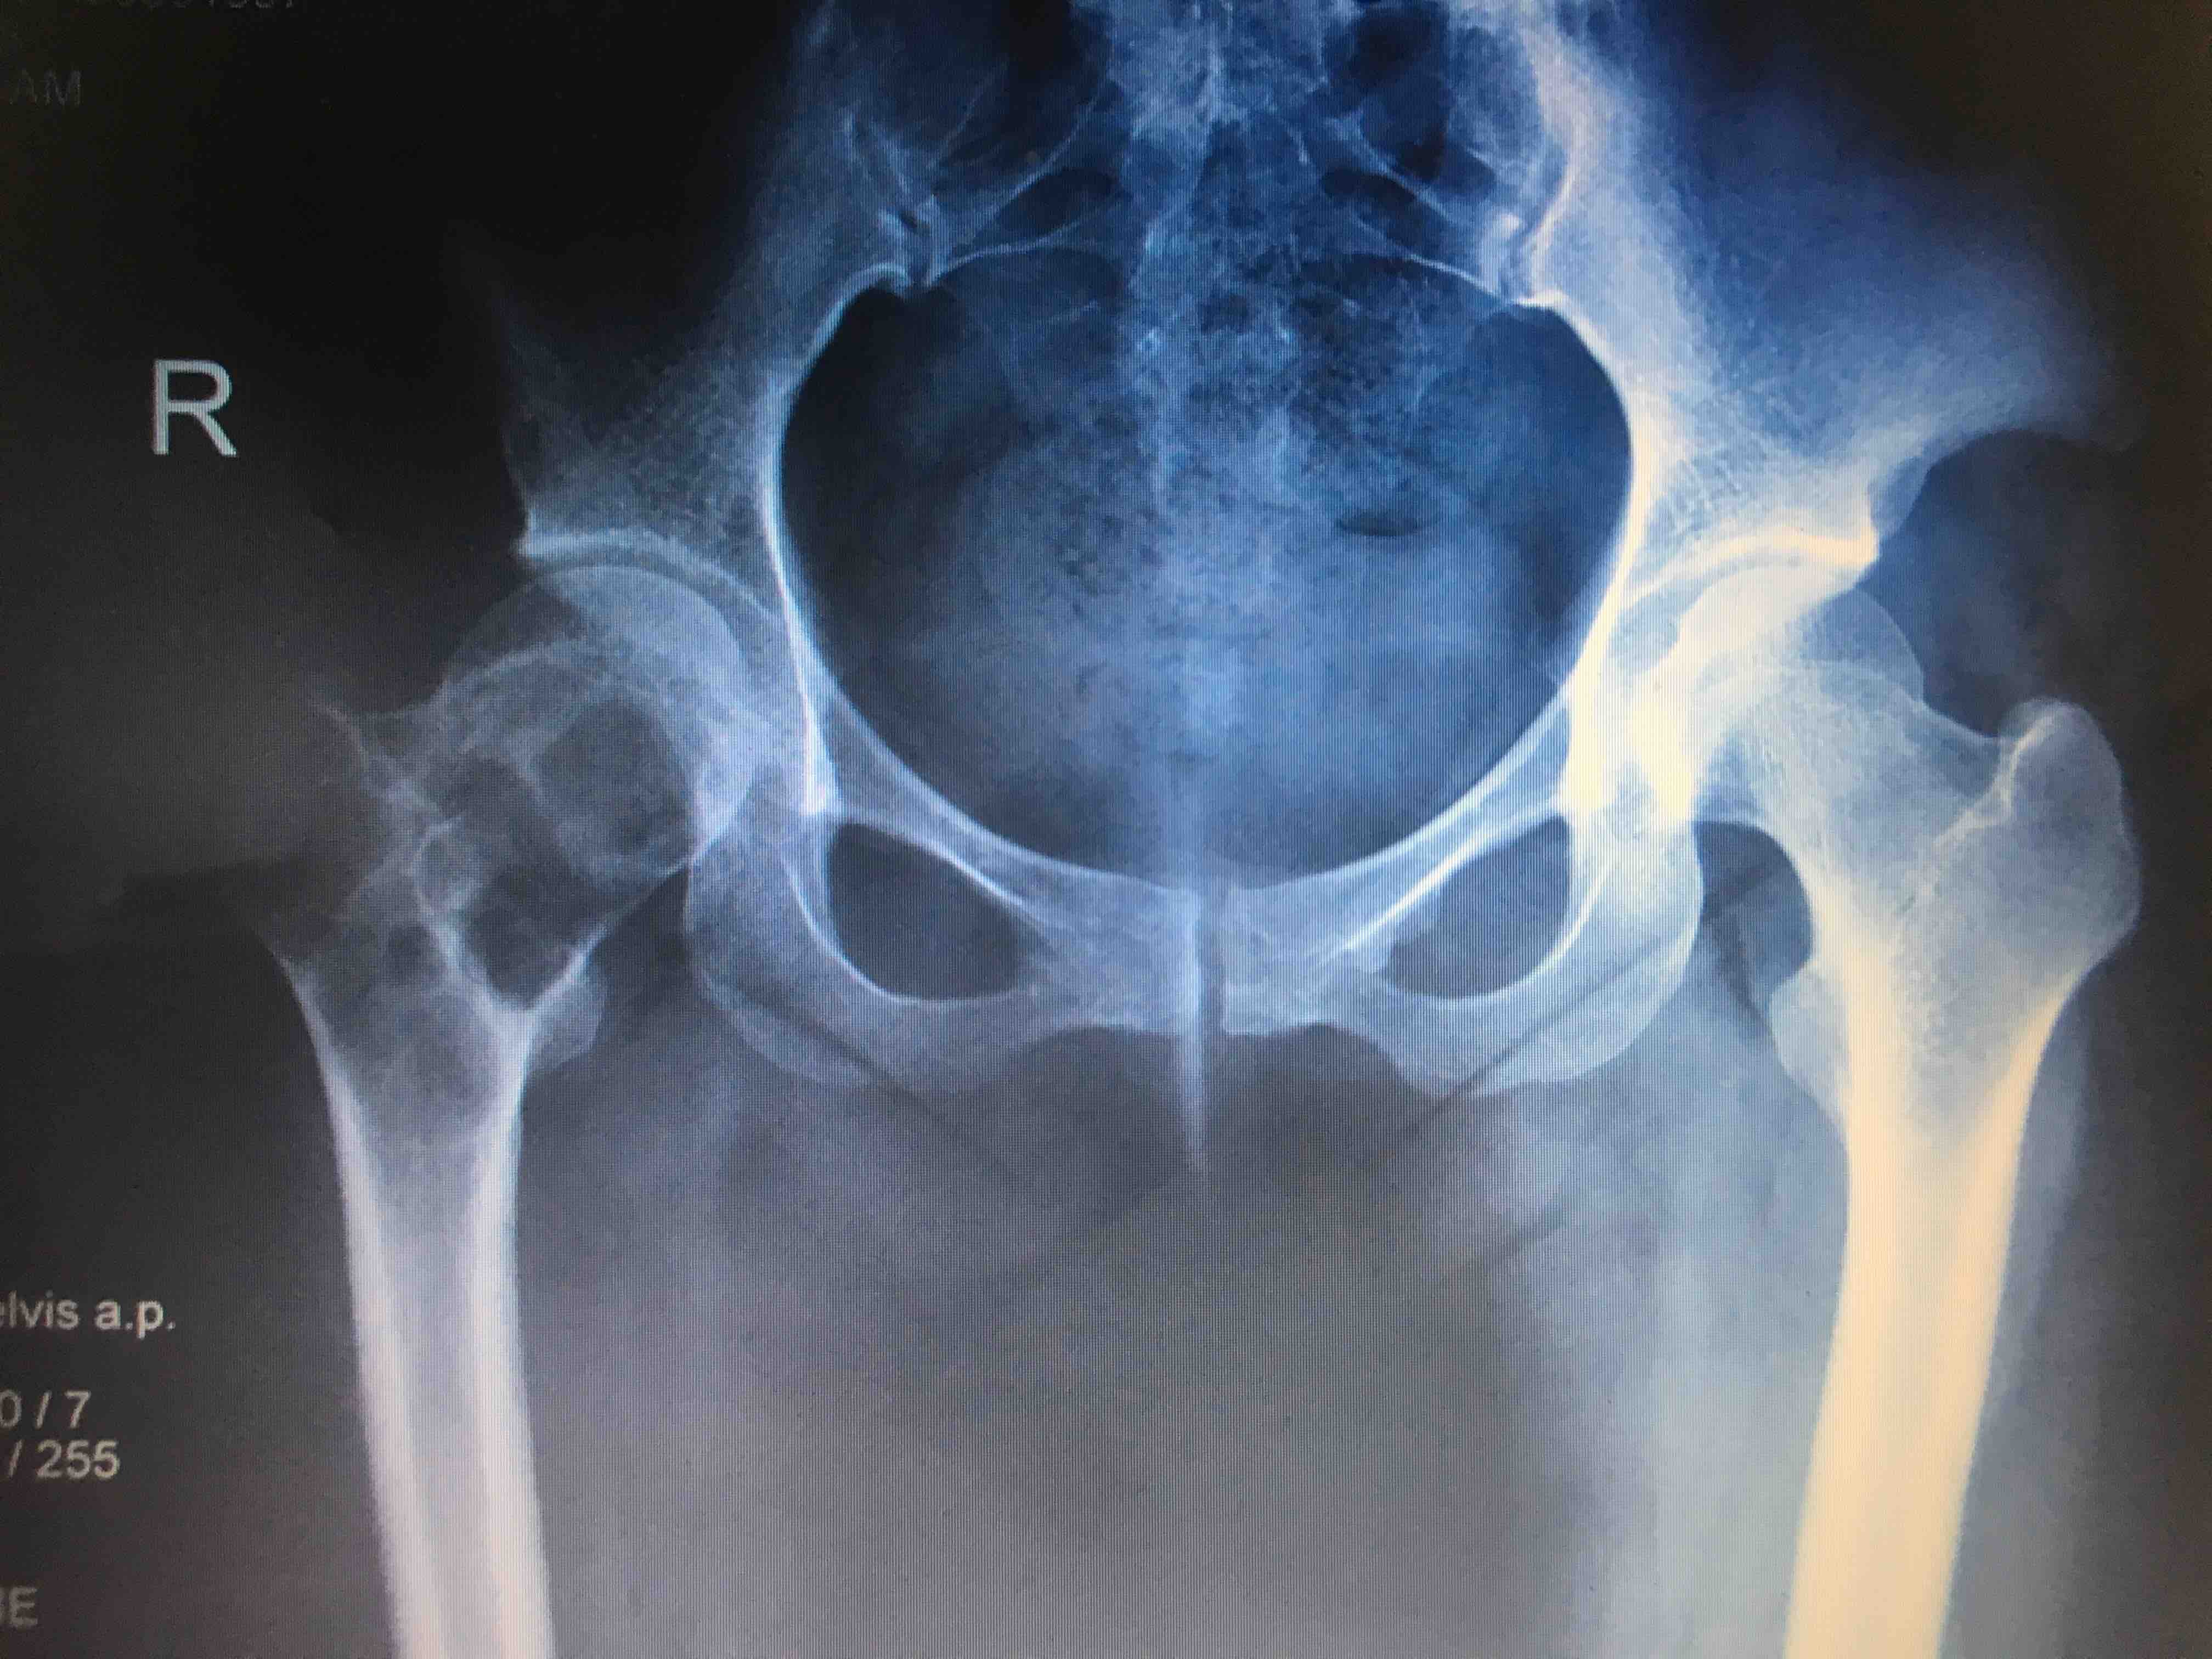

敲黑板:问病史的时候,患者诉左髋关节做过手术,虽然不知道什么手术,但是做"4" 字试验要轻柔或者让患者自己完成,如果强行去做很容易出问题。开骨盆正位片,等待结果。

https://pic.wenwo.com/fimg/466552808.jpg

结果回报大吃一惊,左侧股骨颈肿瘤,大部分骨质被吃没了,就剩下一层菲薄的皮质,如果刚刚做"4" 字试验,用力下压,99%要压骨折了。